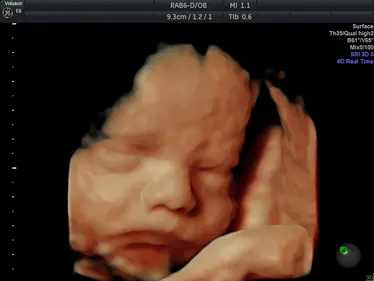

Gallery: 4D Scan Images & Videos

All of the baby scans we perform here at First Encounters are carried out using top-quality ultrasound equipment. For 3D/4D scans, we use the GE Voluson E6, featuring genuine HDLive technology. GE Healthcare are the world’s leading providers of pregnancy scanning equipment, and HD Live scans give an unparalleled level of detail and clarity.

Scroll down to view some examples of the 4D scan images and videos our sonographers are able to capture.

4D Scan Images

During your 3D/4D scan, we’ll capture multiple photographs of your unborn baby, giving you and your family a set of stunning keepsakes that you’ll treasure forever. All of your scan images will be available to download from photocloud™, plus we can provide glossy souvenir photos for you to take home.